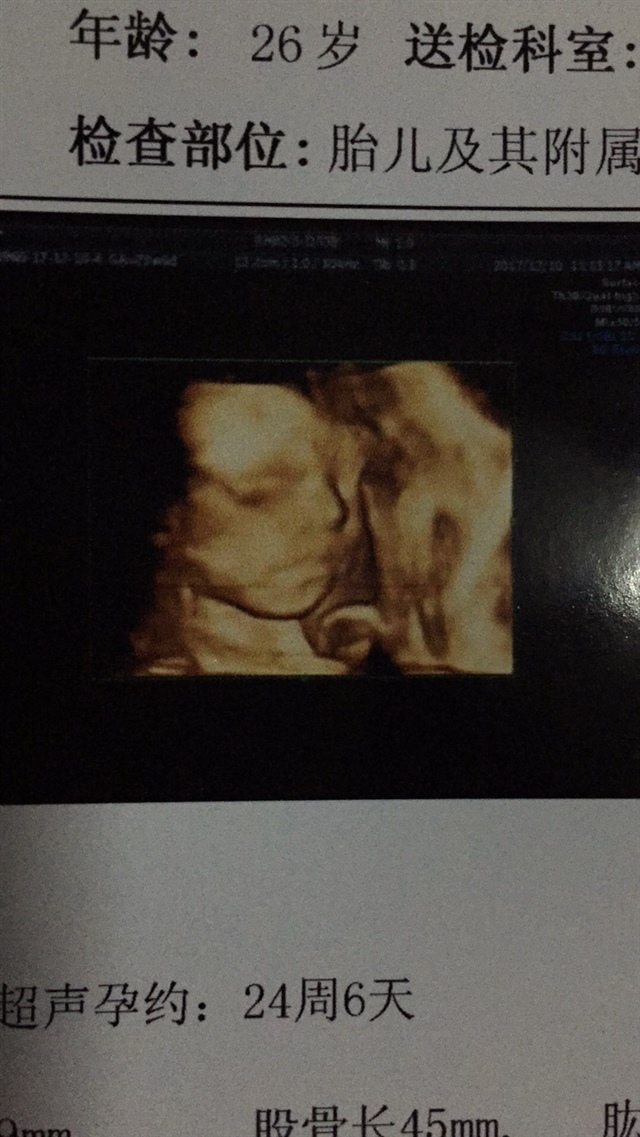

四维你是24周做的?

我的思维好臭好皱 生下来一样怎么办哈哈😄